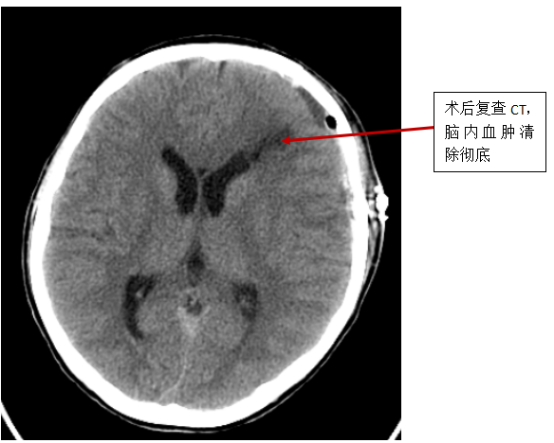

泰康仙林鼓楼医院神经外科胡国庆主任迅速组织起由神经外科、急诊科、影像科、麻醉科、重症医学科组成的抢救团队,对小孙的救治进行讨论并商定手术方案。在抢救团队的共同努力下,历经4个小时的奋战,手术顺利完成。

手术后,小孙被转入重症医学科继续救治,严密观察生命体征。经过半个月悉心治疗,小孙没有留下任何神经功能障碍,痊愈出院。